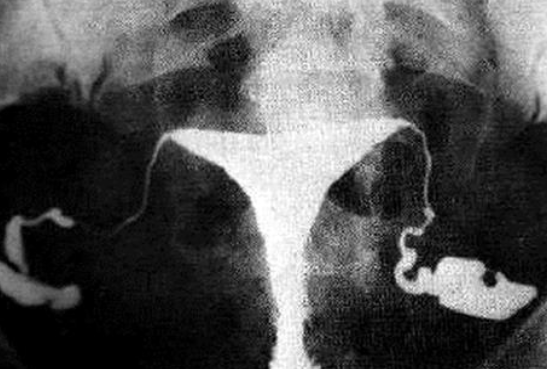

HSG – Unilateral Hydrosalpinx

HSG – Bilateral Hydrosalpinx

Calcified Uterine Leiomyoma

Plain radiograph:

- Calcification in a large uterine fibroid